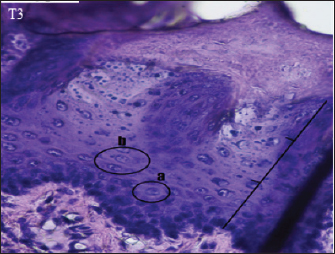

The histopathological appearance of the rat tongue epithelium in the T3 group was close to that of normal epithelium. It is characterized by regular stratification cells. Variations in the shape and size of the nucleus are slight. Hyperchromatic nuclei are found in the basal and parabasal layers. Irregular polygonal cell shapes in the spinosum layer and oval cell shapes in the granulosum layer were also seen in this group (Fig. 5).

Fig. 5. Histopathological appearance of the rat tongue epithelium in group T3, microscope at ×400. (a) irregular polygonal cell shape in the spinosum layer; (b) oval cell shape in the granulosum layer.

In several visual fields, cells in the T3 group had decreased dysplasia, and their condition was similar to that of the negative control group. This suggests that C. cinerariifolium leaf extract at a concentration of 200 mg/kg bw can effectively lower the degree of dysplasia in the oral epithelium. Differences in the terpenoid and flavonoid content of extract and the degree of dysplasia between the treatment groups were reasonably considerable. Other studies have shown that terpineol component in the extract has an anticancer effect by inhibiting the signaling of the transcription factor NF-kB in tumor cells, hence decreasing gene expression in malignancies (Hassan et al., 2010). Terpenoids also function as anticancer agents in human oral cancer cell lines by inducing cell cycle arrest and death in OSCC cells via caspase cascade (Kim et al., 2022). In the extract of C. cinerariifolium leaf, there is also the flavonoid kaempferitin, which can boost the production of the p53 oncogene protein, hence promoting an increase in apoptosis (Siddiqui et al., 2020). The process of inhibiting the production of oncogene proteins and enhancing the expression of tumor suppressor genes can stop aberrant cell proliferation and lower the severity of dysplasia. According to Mutiah et al. (2020), 96% ethanolic extract of C. cinerariifolium (Trev.) leaf based on in silico analysis contains glutamic acid in hydrogen bonds, which inhibits tumor development by blocking angiogenesis.